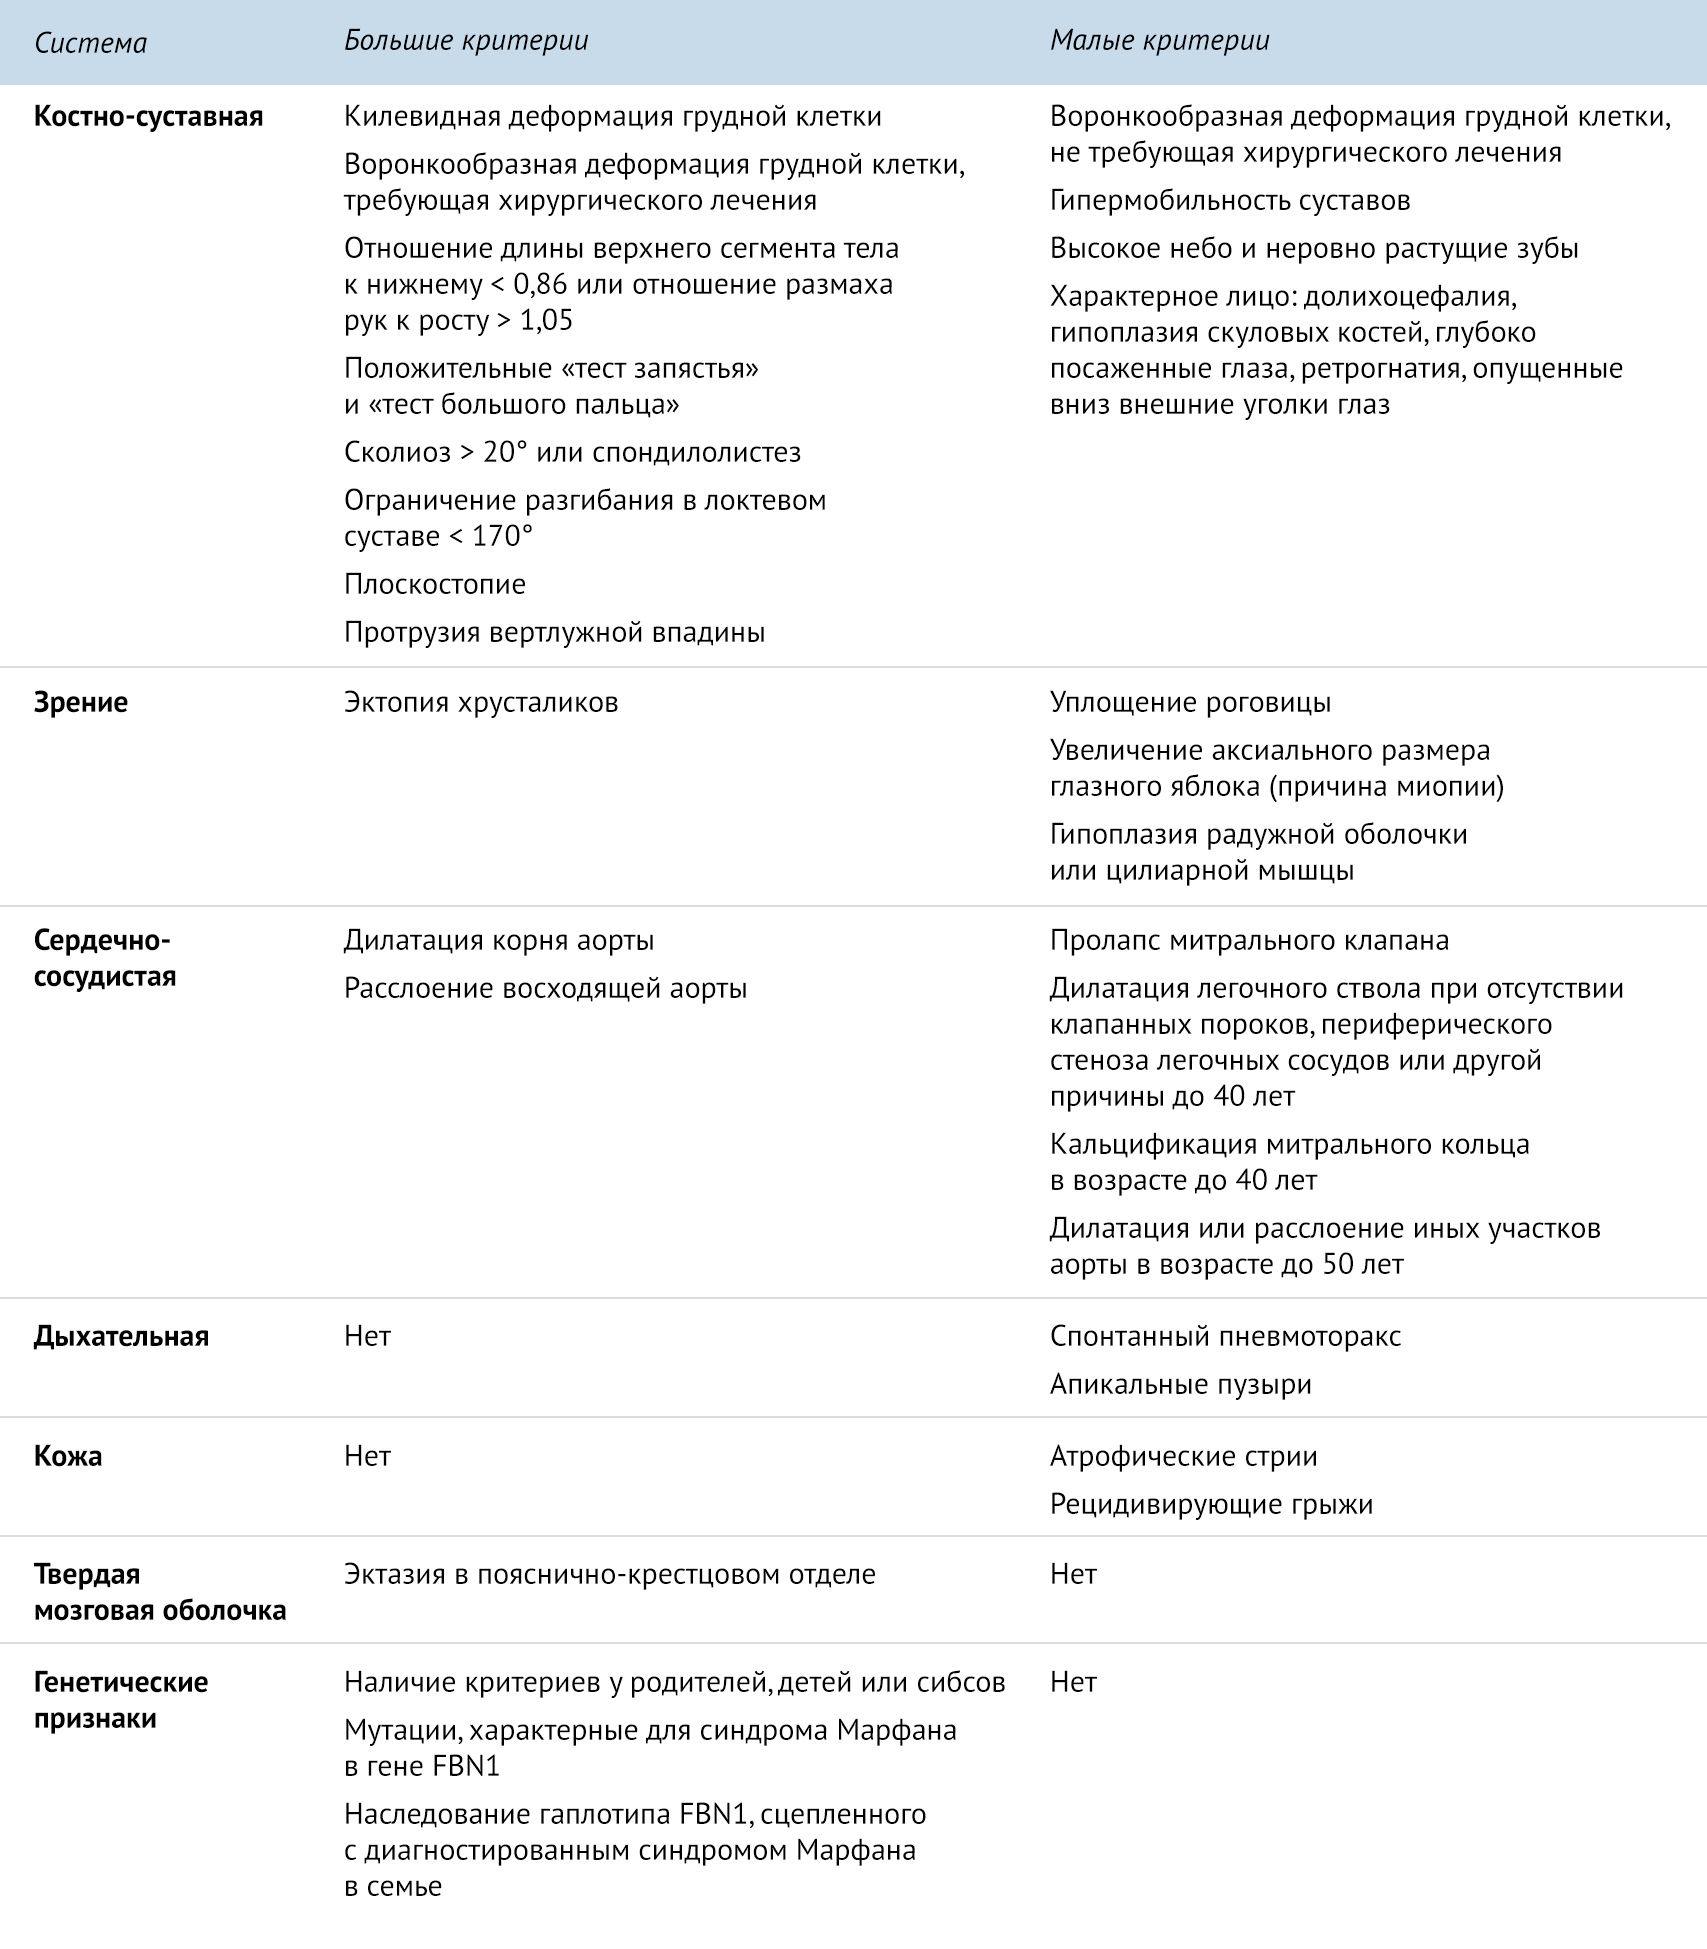

Sindrom marfana tema nauchnoj stati po klinicheskoj medicine chitajte besplatno tekst nauchno issledovatelskoj raboty v elektronnoj biblioteke kiberleninka (Тип файлу jpg)

Sindrom Marfana Tema Nauchnoj Stati Po Klinicheskoj Medicine Chitajte Besplatno Tekst Nauchno Issledovatelskoj Raboty V Elektronnoj Biblioteke Kiberleninka

Sindrom marfana tema nauchnoj stati po klinicheskoj medicine chitajte besplatno tekst nauchno issledovatelskoj raboty v elektronnoj biblioteke kiberleninka (Тип файлу jpg)

Sindrom Marfana Tema Nauchnoj Stati Po Klinicheskoj Medicine Chitajte Besplatno Tekst Nauchno Issledovatelskoj Raboty V Elektronnoj Biblioteke Kiberleninka